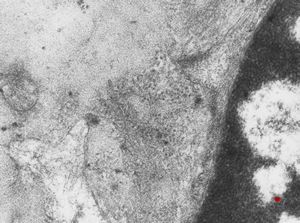

F,40y. | membranous glomerulopathy - lupus erythematodes (tubuloreticular organelle)

F,40y. | membranous glomerulopathy - lupus erythematodes